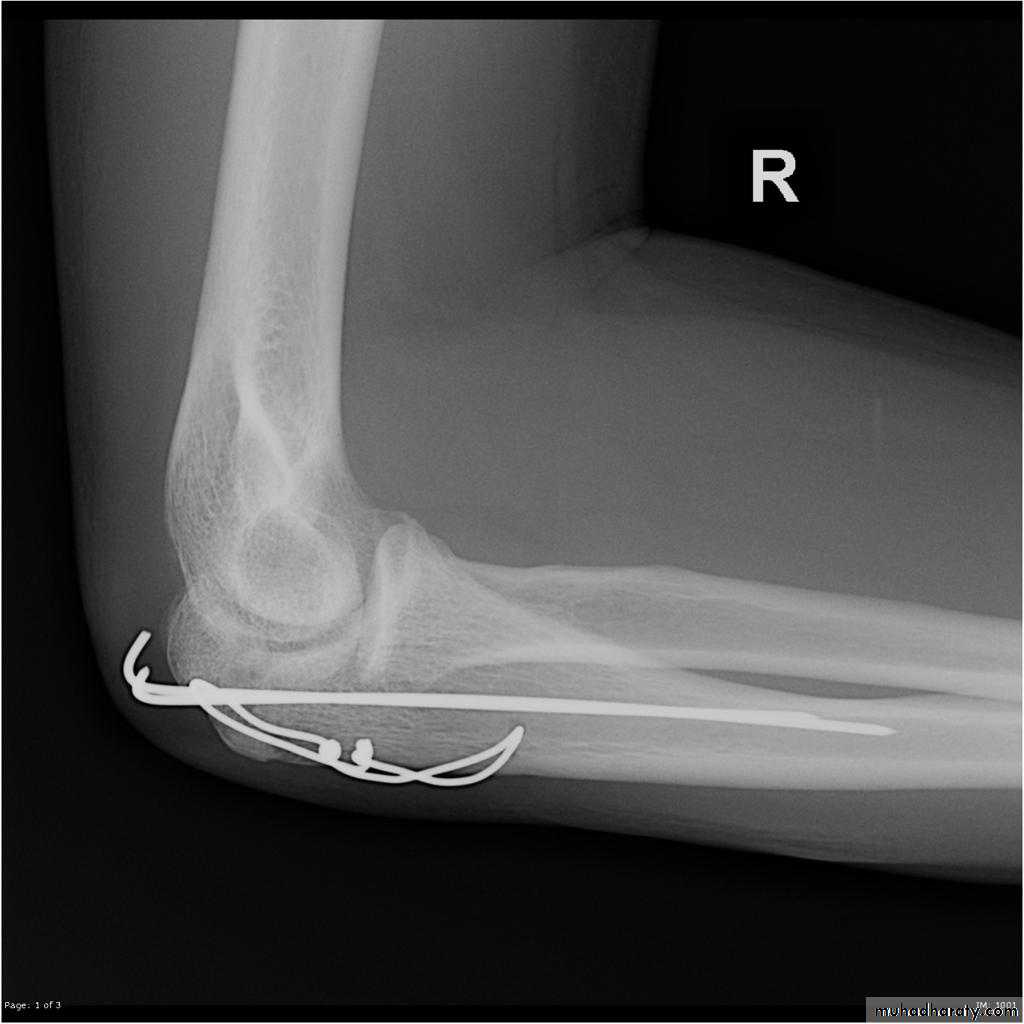

Olecranon Fractures

MOI

Type 1 - direct blow or a fall on the elbow = comminuted #.

Type 2 - Traction when the patient falls onto the hand while the triceps muscle is contracted = transverse #

CF;

Type1-bruise over the elbow, triceps is intact and the elbow can be extended against gravity.Type-2- palpable gap the patient is unable to extend the elbow against gravity.

X-RAY; check the position of the radial head.

Treatment;Type1 splint.

Type2 displaced ORIF. (K wire & tension band wiring).

Complication;

Stiffness.Non union.

Ulnar N.palsy .

Osteoarthritis.